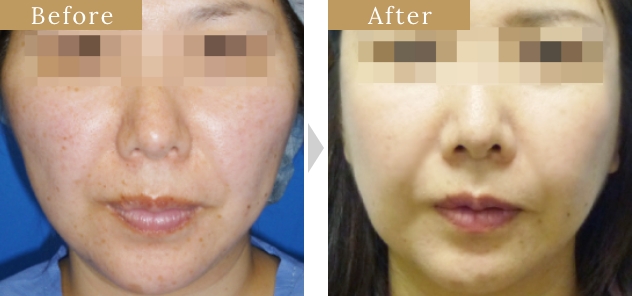

症例